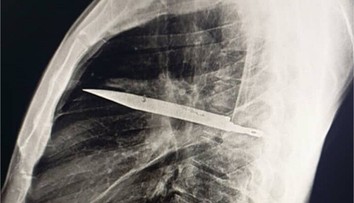

Ilustračná snímka Zdroj: Profimedia